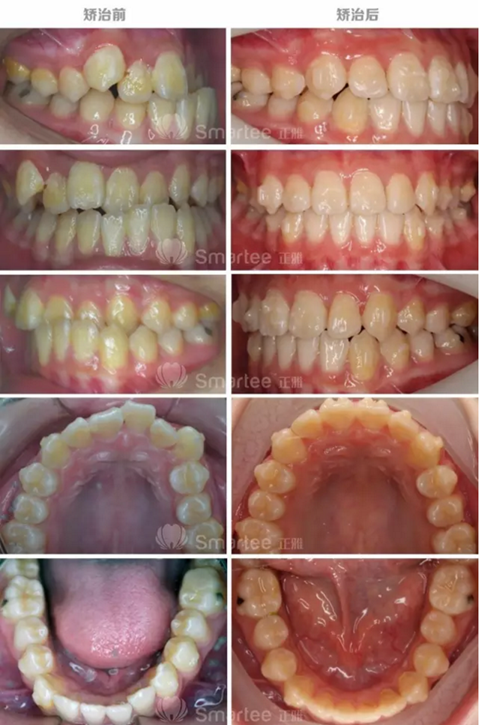

反牙合病例

性別:女

年齡:11歲

主訴:面部左右不對稱,左側(cè)前牙反牙合。

1)安氏Ⅲ類錯(cuò)牙合

2)左側(cè)前牙反牙合

3)前牙區(qū)擁擠,個(gè)別牙扭轉(zhuǎn)

4)上頜中線右偏

(矯治前后反饋情況對比)

1)隱形矯治器配合牙合墊附件,對于前牙反牙合的解除起到了重要作用。

2)通過優(yōu)化附件的使用,很好的整平了spee曲線。

3)通過增加控根附件,11、21做到了良好的控根移動(dòng)。